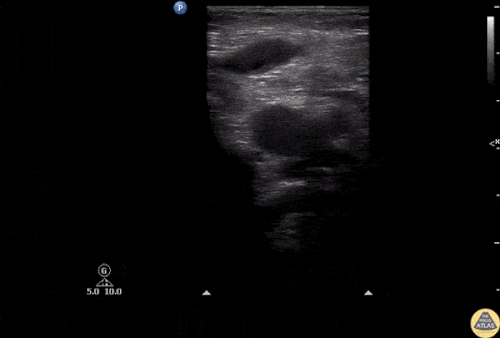

Patolojik DVT USG:

| Sol popliteal vende oklüziv DVT

|

Popliteal DVT

| DVT (Derin ven trombozu)

Büyük safen ven trombozu